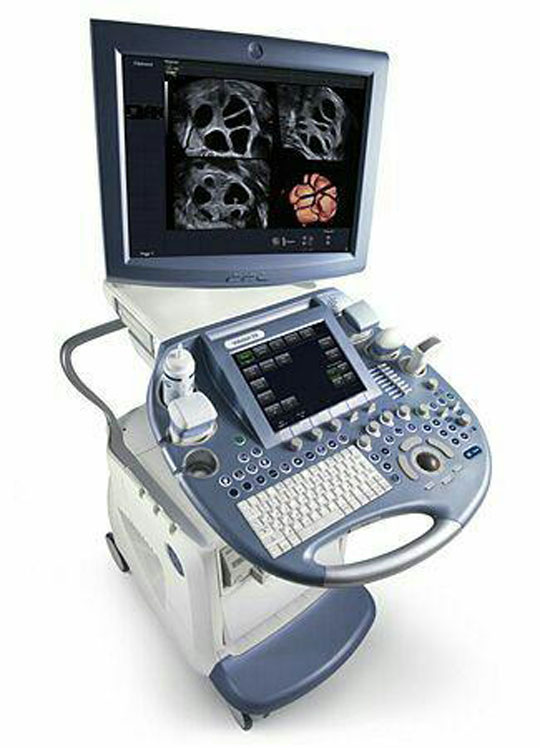

کاربرد و انواع سونوگرافی

کاربرد و انواع سونوگرافیسونوگرافی یا تصویربرداری اولتراسوند، روش تصویربرداری ایمن و بدون درد از اندام های بدن است. و از امواج صوتی استفاده میشود که برای بدن ضرری ندارد . ...

مركز سونوگرافى و راديولوژى شقايق واقع در يوسف آباد تهران با بهره گيرى از عوامل فوق الذكر تلاش كرده است تا در ارائه بهترين خدمات راديولوژى و همچنين بهترين سونوگرافى دقيق در يوسف آباد تهران كه در ذيل فهرست وار آمده است در خدمت عزيزان هموطن درتهران و سرتاسر ايران باشد.

بهترين بررسي هاي روتين وتخصصی و دقيق ترين انواع داپلر يارنگی شامل : سونوگرافى كالر داپلر شريانى و وريدي اندامهاى تحتانى و فوقانى و بررسي دقيق DVT ، داپلر دقيق كليه ها ، سونوگرافى رنگى و داپلر بيضه ها ، بهترين و دقيق ترين سونوگرافى داپلر عروق كاروتيد گردنى وبررسي پلاك ، انسداد و ترومبوز

رادیولوژی و سونوگرافی شقایق تهران یکی از مراکز تخصصی است که با تجهیزات مدرن و به روز میتواند انواع خدمات تشخیصی درمانی در این زمینه را به مراجعین ارائه نماید. آدرس مطب : منطقه شش ٦ - تهران ، یوسف آباد ، خیابان فتحی شقاقی ، بین چهلستون و بیستون ، راديولوژي و سونوگرافى شقايق، دكتر سيف